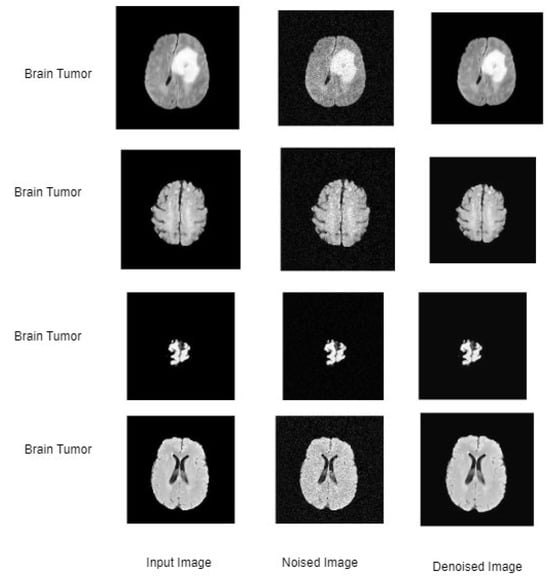

2.4.1. Discussion on MRI Brain Images

3.1. Results and Discussion of ETLFOD_model for Brain Dataset